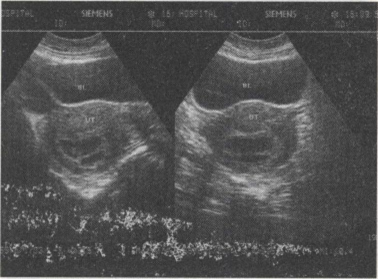

38.女,23岁,停经45天,阴道无异常分泌物,子宫附件声像图如下,图中所示为()